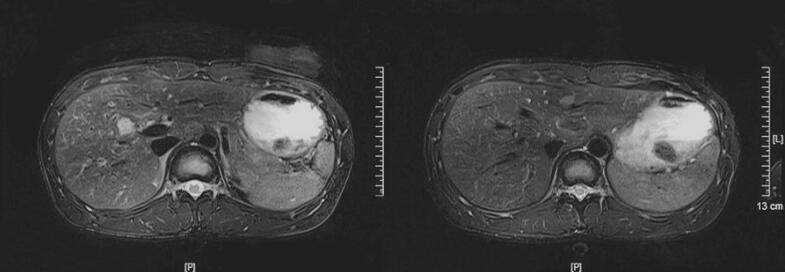

图1 磁共振平扫+增强

肝内多发结节状异常信号,考虑肿瘤性病变,①转移性,②肝原发肿瘤,请结合临床